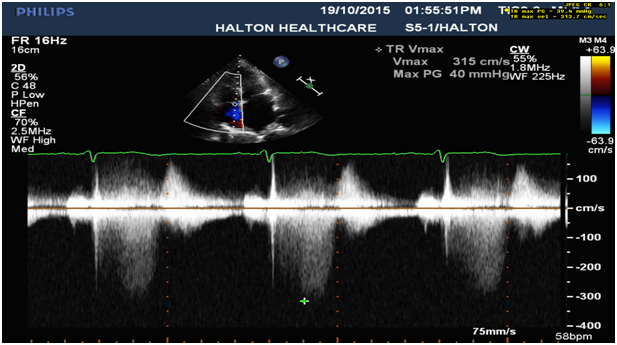

7. Mild pulmonary hypertension (Figure 7).

Figure 7: Tricuspid regurgitation: Mildly increased right ventricular systolic pressure, 43 mmHg.